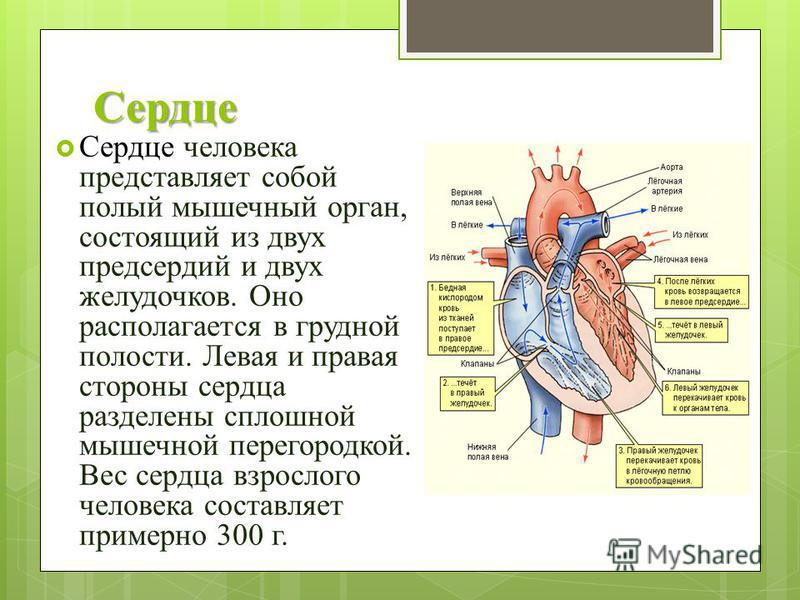

Сердце у человека располагается в грудной полости.

Расположение сердца у человека.

Анатомическое расположение сердца.

Сердце в грудной клетке расположено.

Где расположено сердце у человека анатомия.